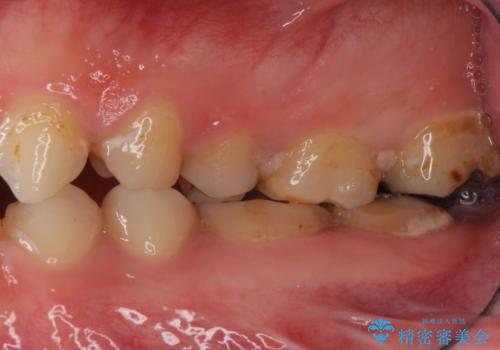

奥歯の咬み合わせも良くなったと喜んで頂けました。

下顎はホワイトニングを行っております。

「今後も繰り返しホワイトニングをして白さを追求していきます!」とおっしゃって下さいました。

クラウンの種類:オールセラミッククラウン スタンダード